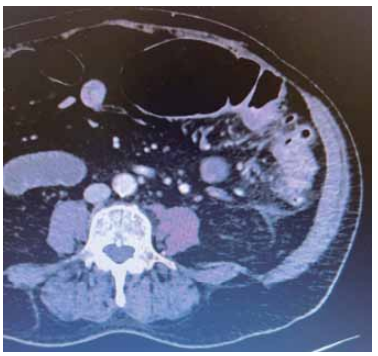

Paciente de 71 anos, sexo feminino, apresenta queixa de dor em hemiabdome esquerdo. Em bom estado geral, sem febre, vômito ou alterações do trato gastrointestinal. Ao exame físico, dor à palpação de flanco esquerdo com descompressão brusca interrogada.

Obteve-se a seguinte imagem na tomografia realizada na investigação:

(Arquivo pessoal; imagem utilizada com autorização)